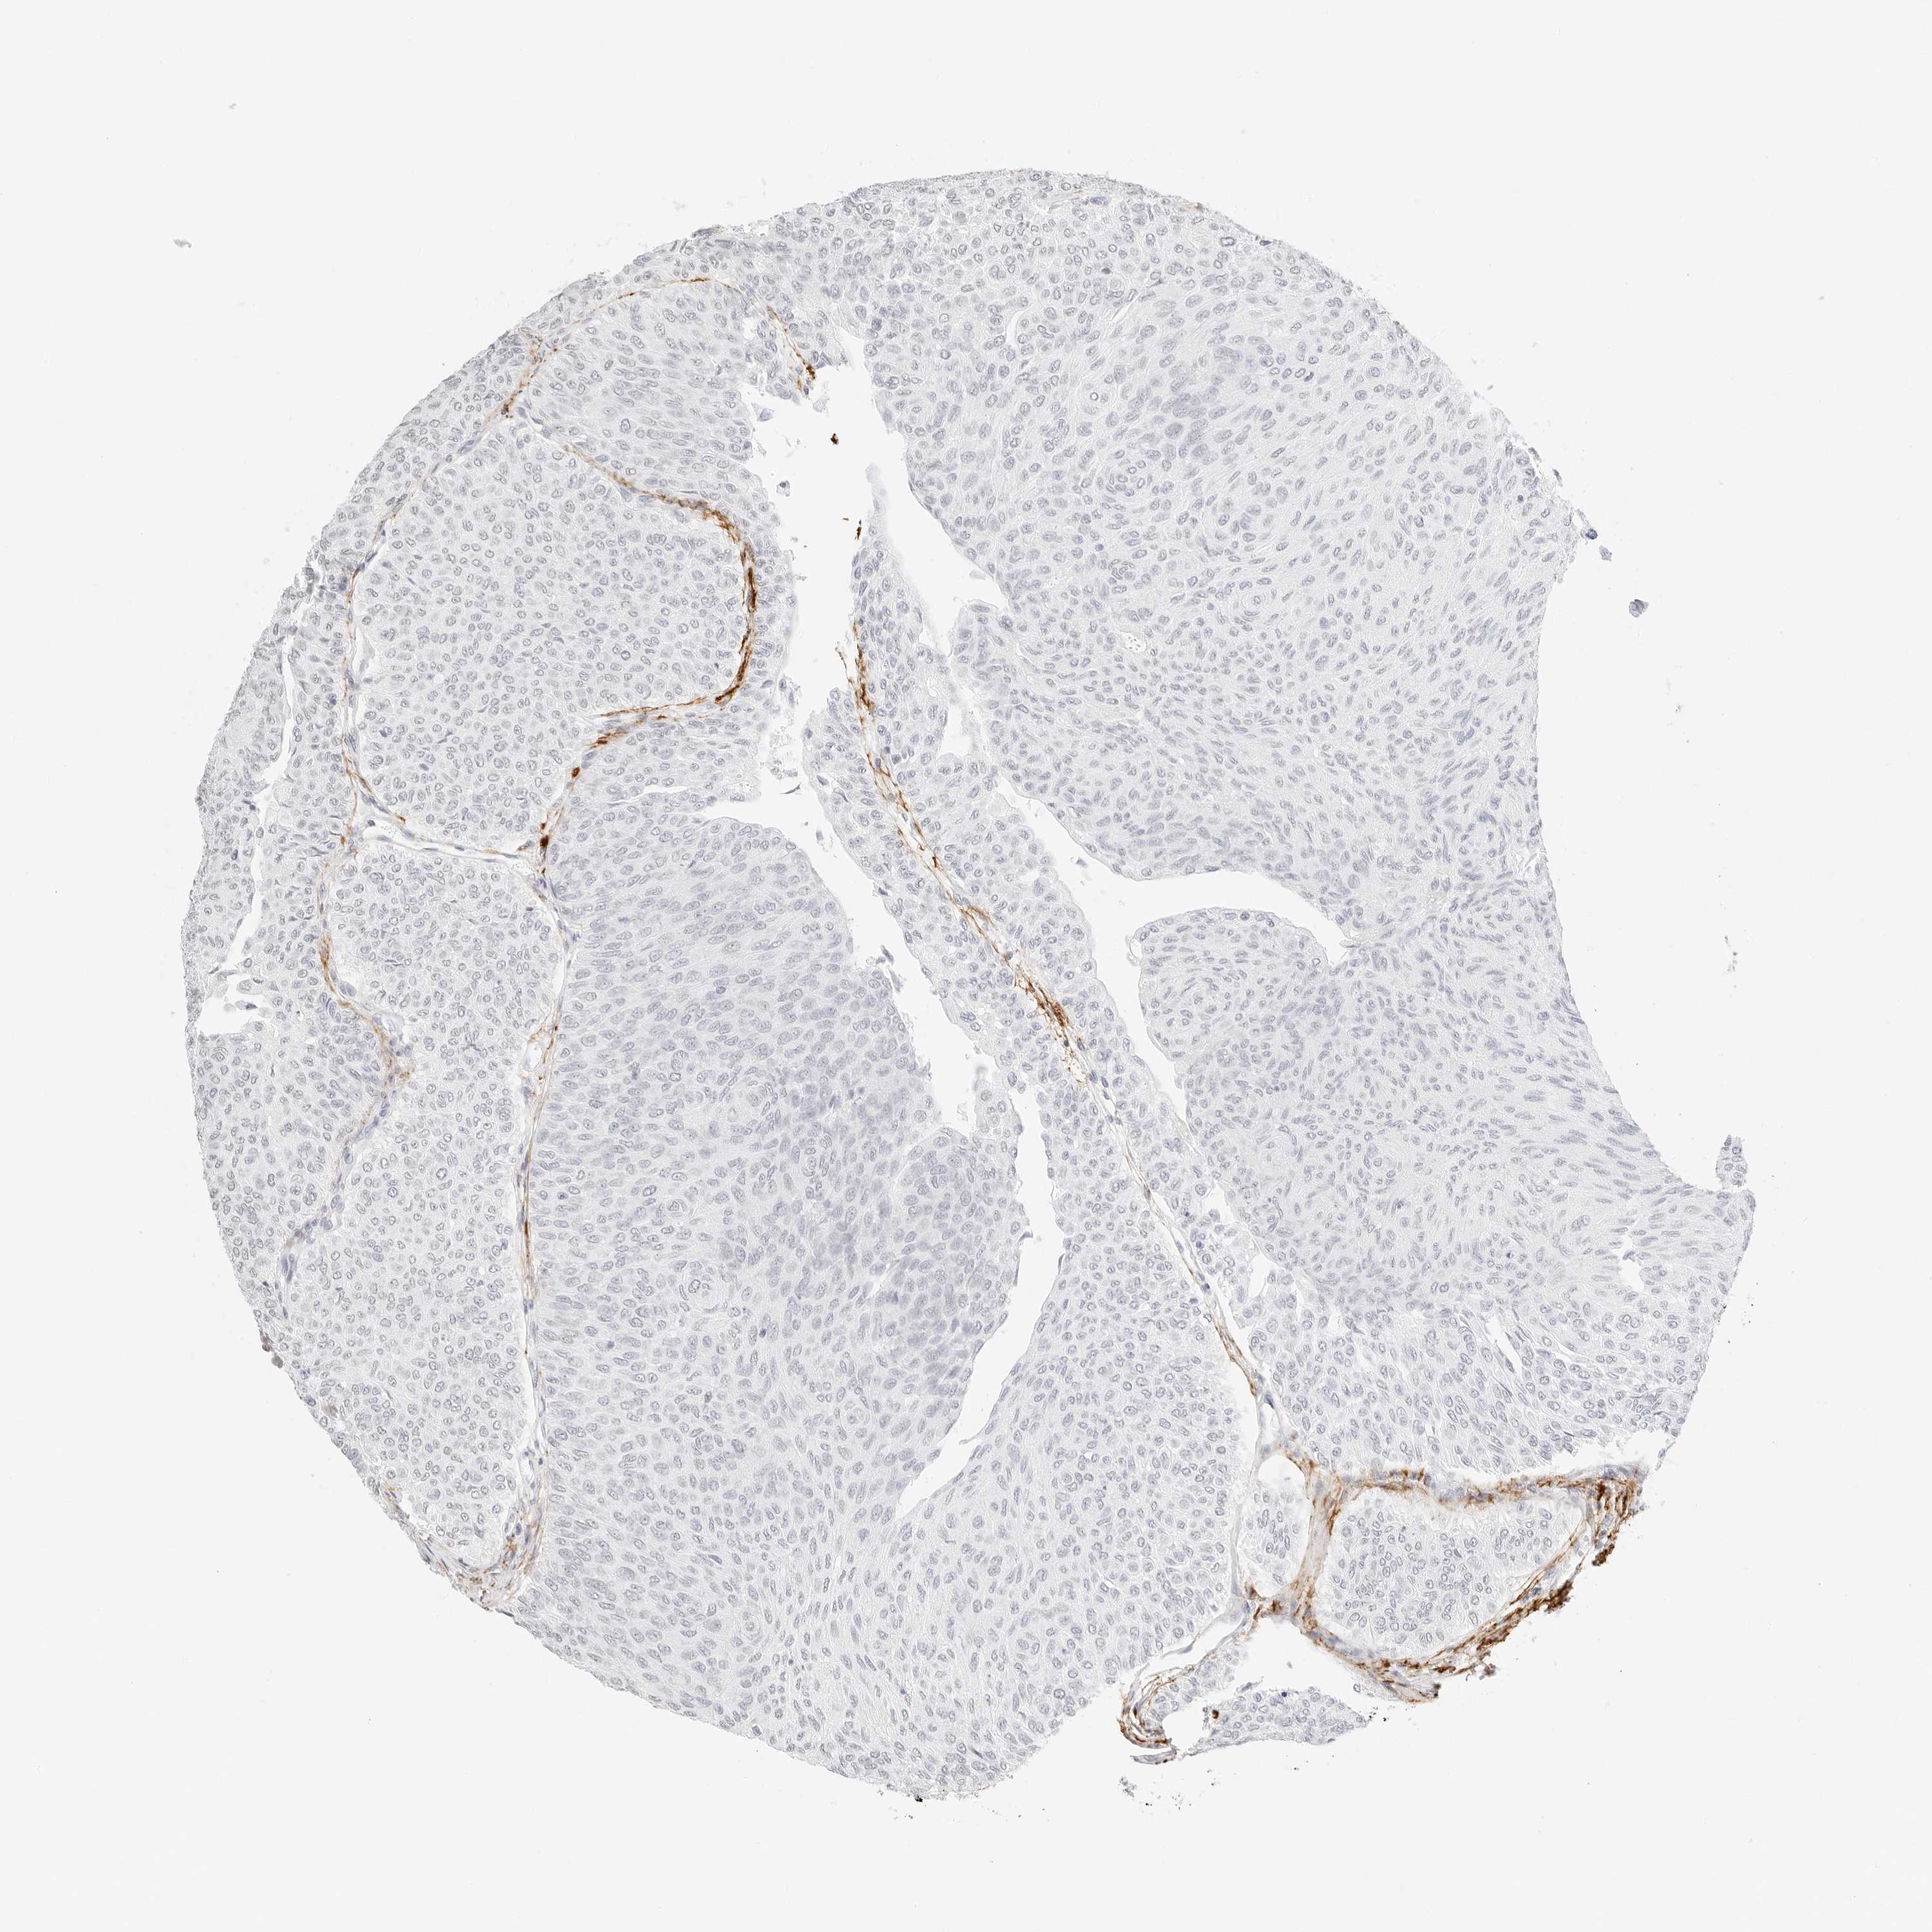

UROTHELIAL CANCER - Protein expressioni

A mouse-over function shows sample information and annotation data. Click on an image to view it in a full screen mode. Samples can be filtered based on level of antibody staining by selecting one or several of the following categories: high, medium, low and not detected. The assay and annotation is described here.

Note that samples used for immunohistochemistry by the Human Protein Atlas do not correspond to samples in the TCGA dataset.

Antibody stainingi

Antibody staining in the annotated cell types in the current human tissue is reported as not detected, low, medium, or high, based on conventional immunohistochemistry profiling in selected tissues. This score is based on the combination of the staining intensity and fraction of stained cells.

Each image is clickable and will lead to virtual microscopy that enables deeper exploration of all samples and also displays staining intensity scores, fraction scores and subcellular localization as well as patient and tissue information for each sample.

Antibody HPA000848

Antibody HPA000868

Antibody CAB025843

Staining

High

Medium

Low

Not detected

Intensity

Strong

Moderate

Weak

Negative

Quantity

>75%

75%-25%

<25%

None

Location

Nuclear

Cytoplasmic/membranous

Cytoplasmic/membranous,nuclear

Urothelial carcinoma, High grade

Urothelial carcinoma, Low grade